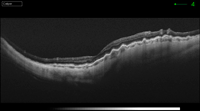

La angiografía fluoresceínica tiene un papel destacado en los pliegues de reciente aparición porque revela el patrón característico de hiperfluorescencia en las crestas combinada con hipofluorescencia en los valles (Figura 1). La tomografía de coherencia óptica (OCT) tiene una especial utilidad en diferenciar los pliegues coroideos de los pliegues retinianos secundarios a patología de la interfase vítreo-retiniana (Figura 2A y Figura 2B)3. Los últimos son más finos, irregulares y menos pigmentados; no se visualizan en la angiografía y la OCT revela su causa (membrana epirretiniana, tracción vítreo-macular…). Recientemente se ha demostrado que los grosores coroideos subfoveales medidos con OCT son mayores en los pacientes con pliegues en comparación con la población normal4. La autofluorescencia es una técnica útil y además no invasiva en la demostración del típico patrón que muestra la angiografía. Se diferencia de ella que el patrón de líneas claras y oscuras aparece de forma inversa (las crestas son hipoautofluorescentes y los valles hiperautofluorescentes)5.

Figura 2B. OCT pliegues coroideos en el caso de una maculopatía por hipotonía en una cirugía filtrante de glaucoma.